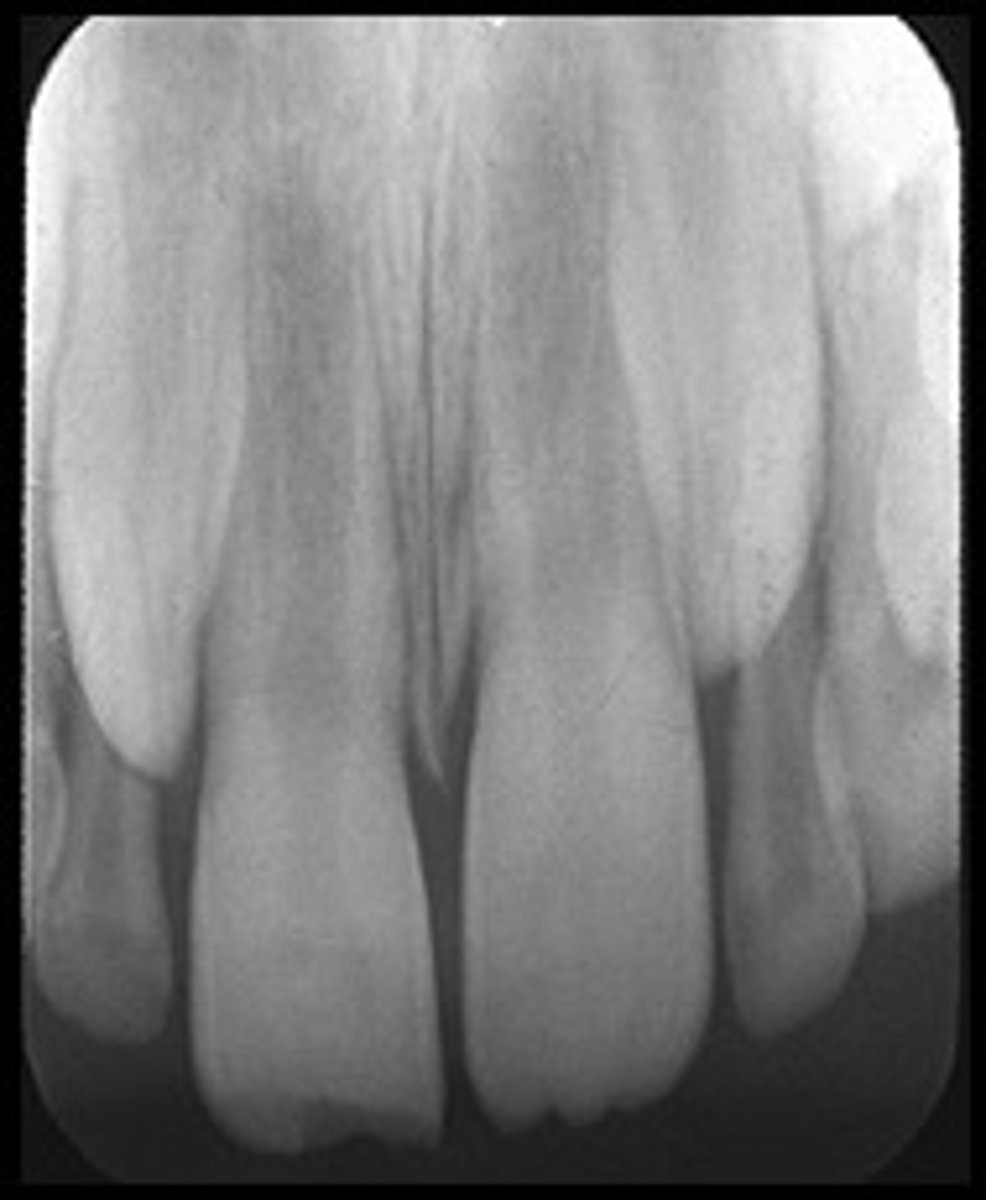

Underexposed Receptor

Receptor

May occur with digital sensors or film

Appearance

The image appears light or low in density.

Cause

The receptor was underexposed.

Correction

Check the exposure time, kilovoltage, and milliamperage settings on the x-ray machine before exposing the receptor.

<p>Receptor</p><p>May occur with digital sensors or film</p><p>Appearance</p><p>The image appears light or low in density.</p><p>Cause</p><p>The receptor was underexposed.</p><p>Correction</p><p>Check the exposure time, kilovoltage, and milliamperage settings on the x-ray machine before exposing the receptor.</p>